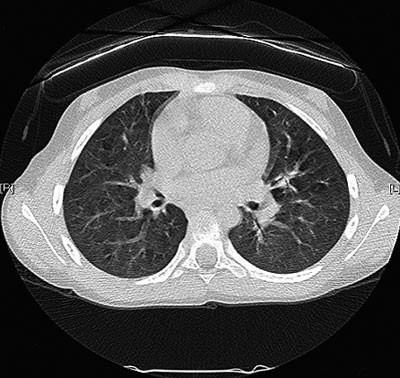

Dosereduksjonen til brystene er betydelig ved bruk av kun ett lag vismut, og ett lag vismut ga mindre artefakter, støy og herdingseffekter enn to og tre lag. På bakgrunn av dette ble bruk av skjoldet med ett lag vismut vurdert som trygt, og det ble bestemt at skjoldet skulle benyttes på pasienter (fig 4). Ved Ullevål universitetssykehus er ett lag vismut nå i rutinemessig bruk som strålebeskyttelse av brystene til jenter under 16 år som kommer til aksial høyoppløsnings-CT av lungene. Skjoldet plasseres over 1 cm skumgummi og er laget i ulike størrelser for å passe best mulig til barna som kommer inn til undersøkelse. Dette er viktig for å unngå artefakter (striper i bildene) som følge av at skjoldet henger for langt ned på sidene. Av hygieniske grunner pakkes skjoldene inn i plast, og festes deretter på pasienten med tape. Dette gjør at både plast og tape enkelt kan fjernes etter undersøkelsen, hvilket ikke er mulig hvis skjoldene festes direkte med tape uten plast mellom. CT-bildene av unge jenter med vismut over brystene ser eksempelvis ut som i figur 5. Bildene vurderes som diagnostisk tilfredsstillende av barneradiolog, da artefaktene rundt skjoldet verken når inn gjennom thoraxveggen eller påvirker fremstillingen av bein- og bløtvev.